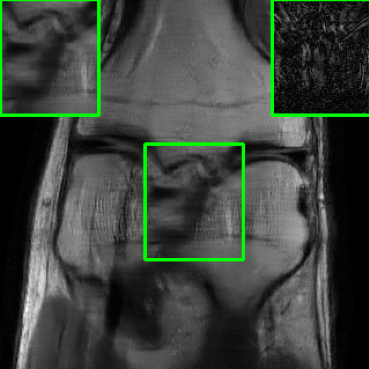

Results for the FastMRI Knee Dataset: In Fig 5 and Fig 7, we report PSNR and SSIM results of different methods at two sampling acceleration factors for the knee dataset. Therein, we observe quite similar outcomes to those reported in Fig 3. Figs. 6 and 8 show reconstructed images by different methods for knee scans at 4x and 8x undersampling, respectively. We observe that SMUG and Weighted SMUG show fewer artifacts, sharper features, and fewer errors when compared to Vanilla MoDL and other baselines in the presence of the worst-case perturbations.

Results on Adversarial Perturbation Strength: In Fig. 9 presents average PSNR results over the test dataset for the considered models under different levels of worst-case perturbations (i.e., attack strength ). We used the knee dataset for this experiment. We observe that SMUG and weighted SMUG outperform RS-E2E, vanilla MoDL, and Deep-Eq across all perturbation strengths. When compared to Score-MRI and AT, our proposed methods consistently maintain higher PSNR values for moderate to large perturbations (less than ). For instance, when , weighted SMUG reports more than 1 dB improvement over AT and Score-MRI.